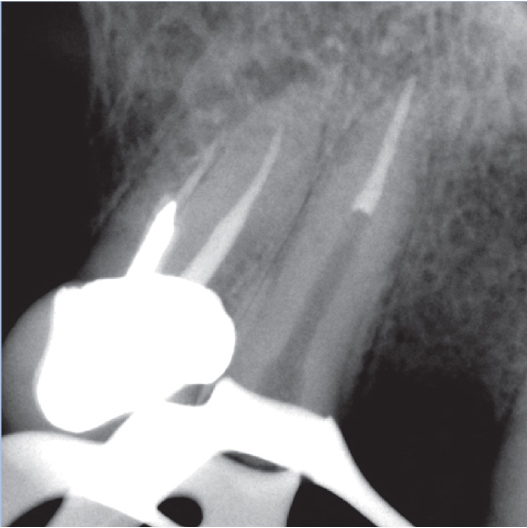

Before

Before Root Canal treatment